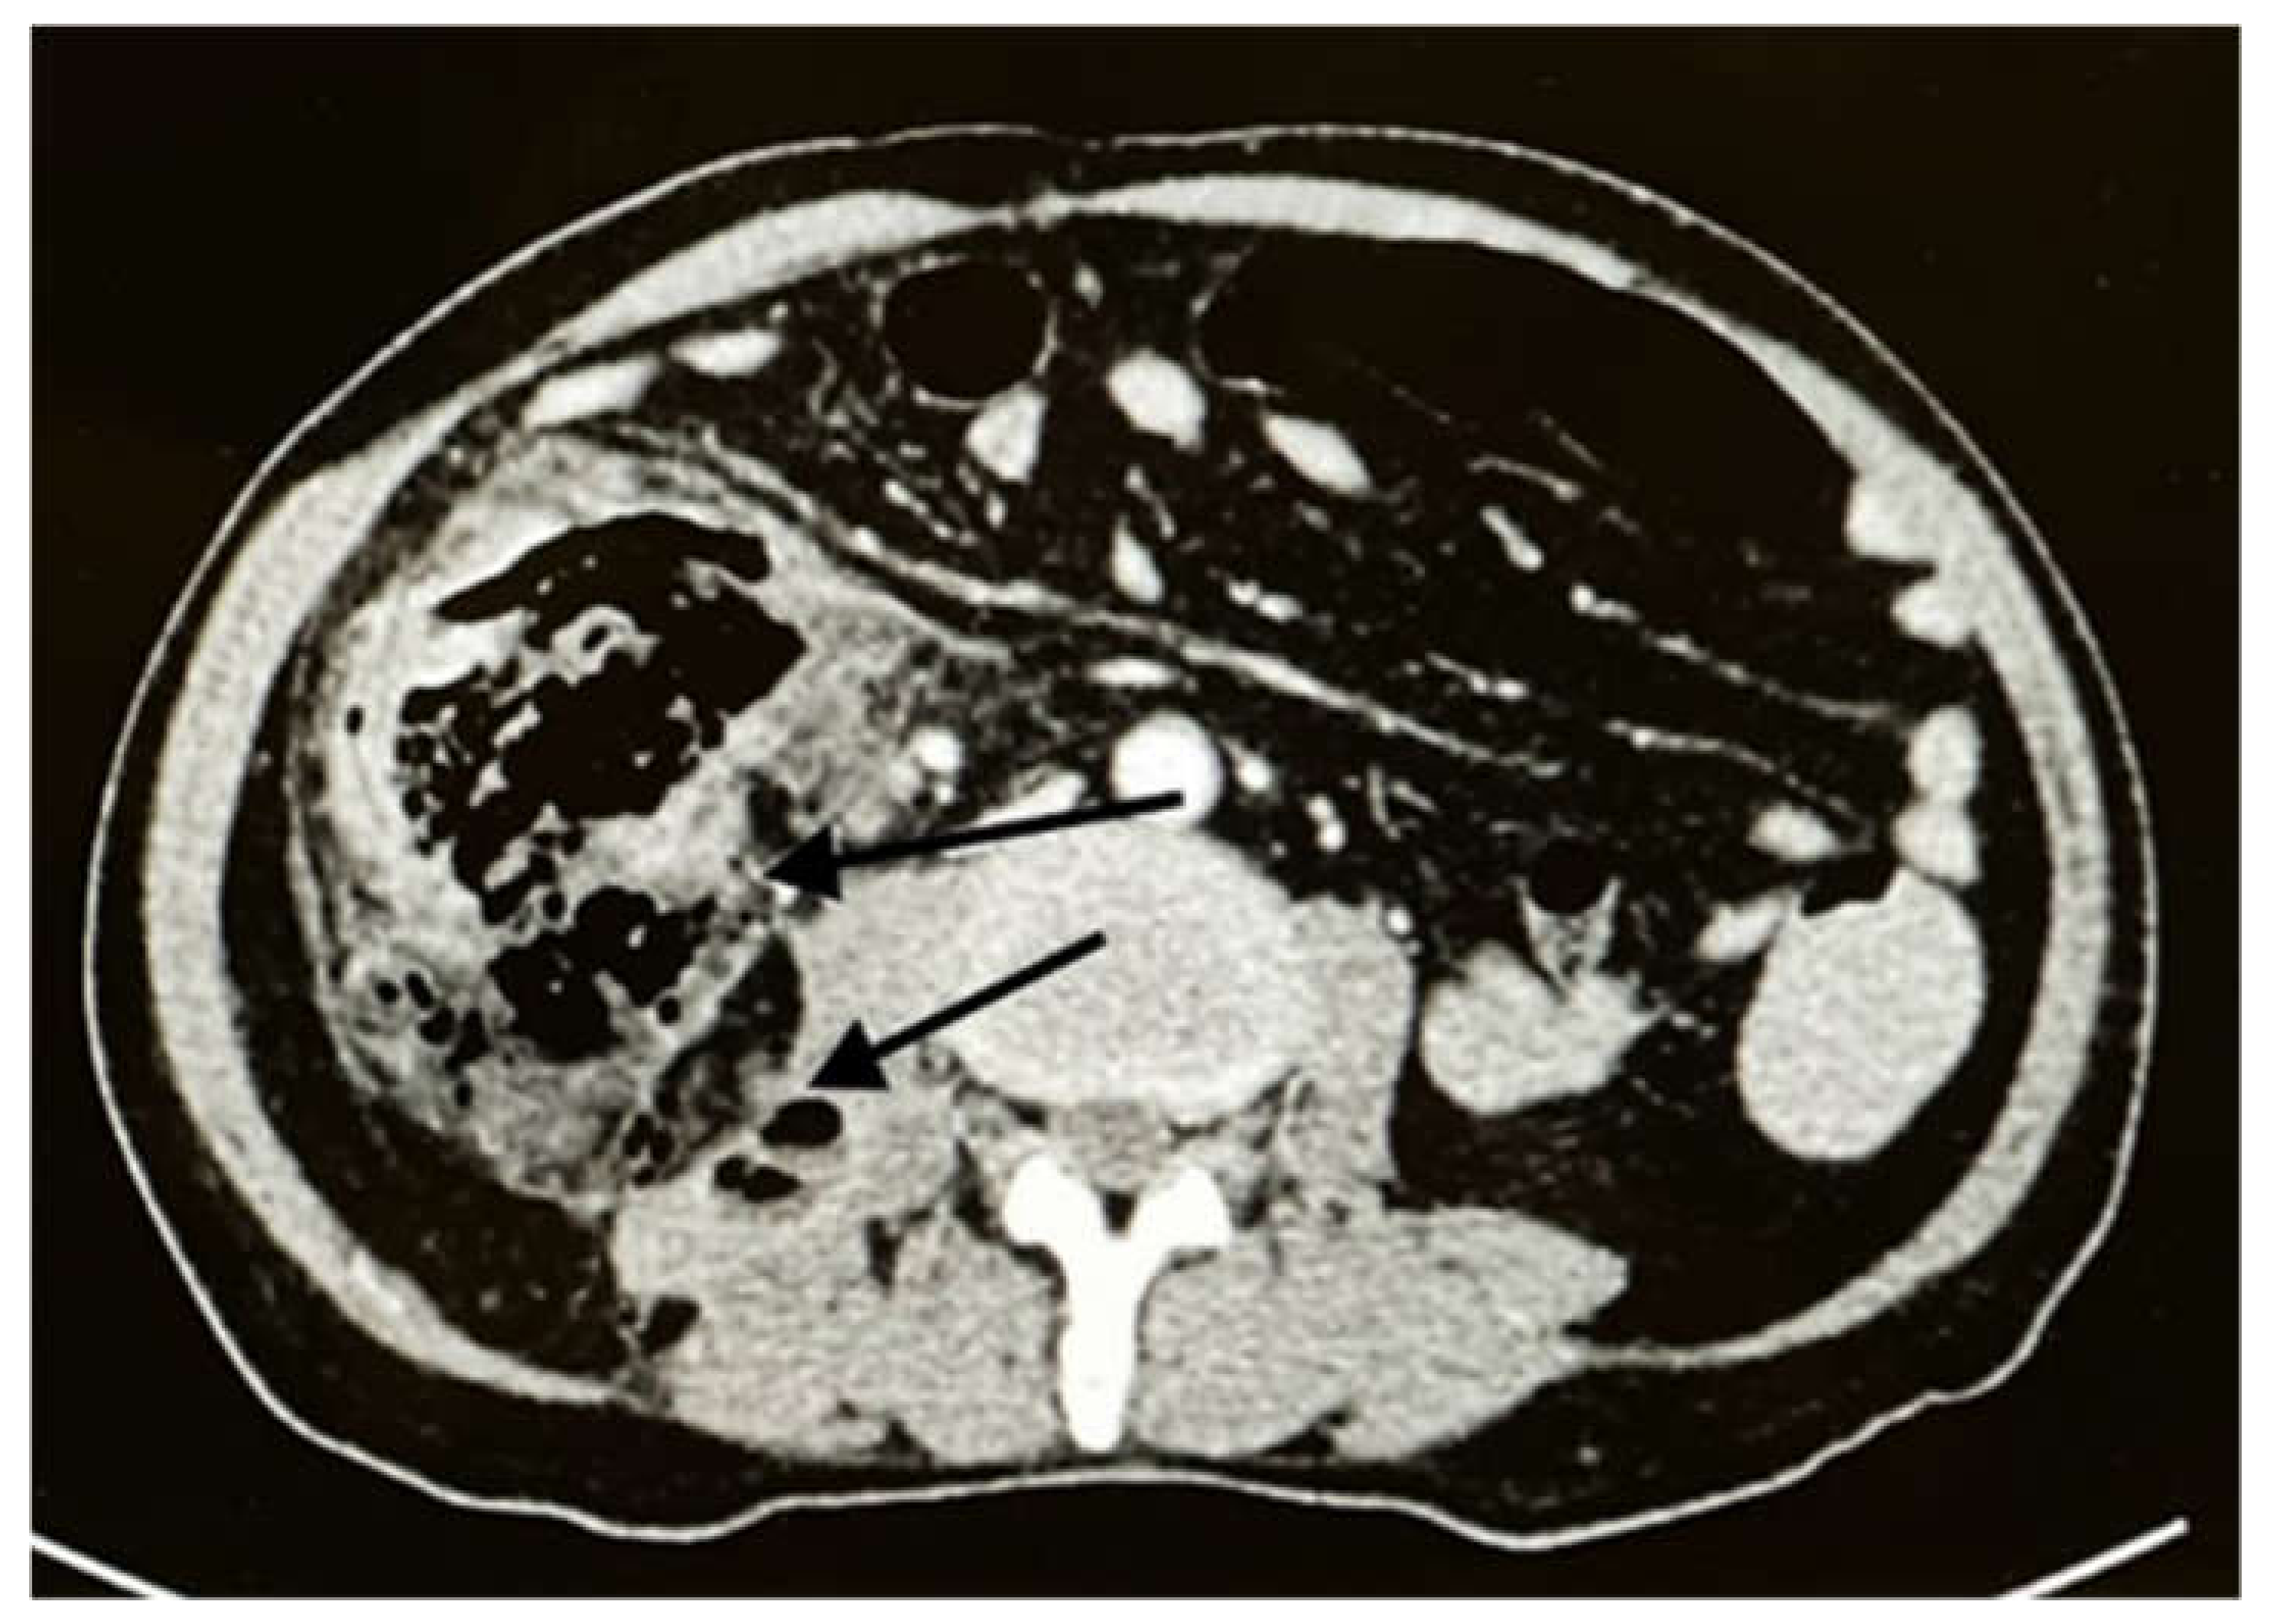

2. Case